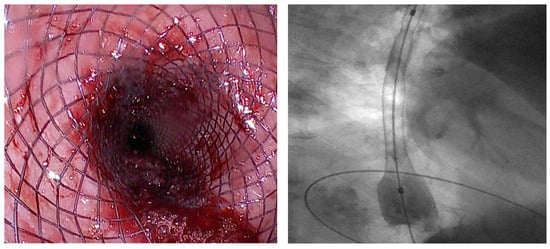

3.1.3. VAC Stent

SEMS vs. VAC Stent

3.2. Malignant Dysphagia (Esophageal Cancer)